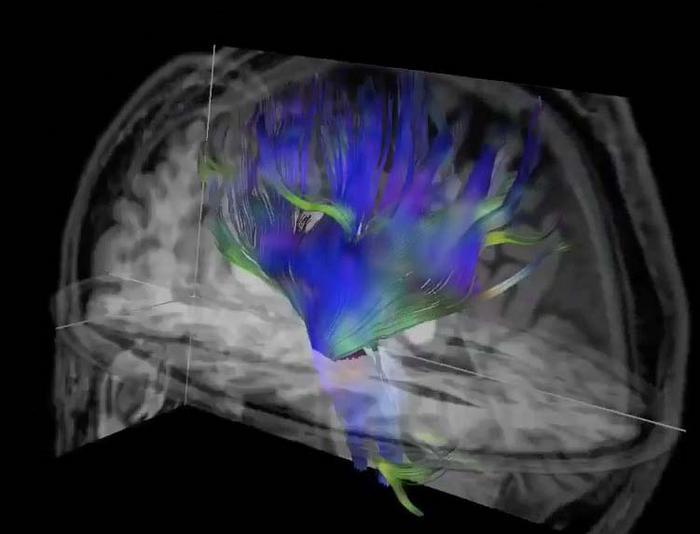

Par la suite et de façon régulière, chaque joueur était soumis à une IRM de diffusion, basée sur l’imagerie par résonance magnétique (IRM), une technique permettant de mesurer la distribution et le mouvement au niveau microscopique des molécules d’eau dans leur cerveau et ainsi d’évaluer les modifications dans la microstructure de l’organe.

Les chercheurs suspectent que cette baisse des performances pouvait être la conséquence d’une porosité accrue entre la matière grise et la matière blanche du cerveau. Normalement, il existe une frontière très nette entre la première, qui contient les corps cellulaires des neurones, et la seconde qui renferme les fibres nerveuses (les axones), des neurones. Des chocs répétés au cerveau pourraient entamer l’intégrité de cette frontière et nuire ainsi à la transmission de l’information neuronale.